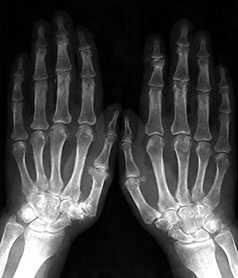

Остеартроз проксимальных и дистальных межфаланговых суставов

Стандартная рентгенография кистей проводится в прямой проекции. Пальцы расположены вместе, кисти лежат ровно на кассете на одной линии с осью, проходящей через предплечья и запястья.

Начальные проявления (соответствуют 1-2 стадиям артроза по Kellgren):

Небольшие заострения краев или остеофиты с нерезким субхондральным остеосклерозом; мелкие, субхондрально расположенные кисты при нормальной или слегка суженной суставной щели, мелкие кальцификаты в мягких тканях в области боковых краев суставных поверхностей костей.

Выраженные изменения (соответствуют 3-4 стадиям артроза по Kellgren):

Умеренно выраженные или крупные остеофиты, деформация краев суставных поверхностей, значительное сужение суставных щелей, остеосклероз (узелки Гебердена в дистальных межфаланговых суставах и узелки Бушара в проксимальных), кисты со склеротическим ободком, краевые дефекты суставных поверхностей, при этом костные выступы с одной стороны могут вклиниваться в другую. Обычно краевые дефекты окружены зоной остеосклероза (рис. 3).

Рис. 3. Обзорная Rо-графия кистей.

Множественные артрозы дистальных и проксимальных межфаланговых суставов. Множественные узелки Гебердена и Бушара. Выраженный артроз 1-го левого запястнопястного сустава